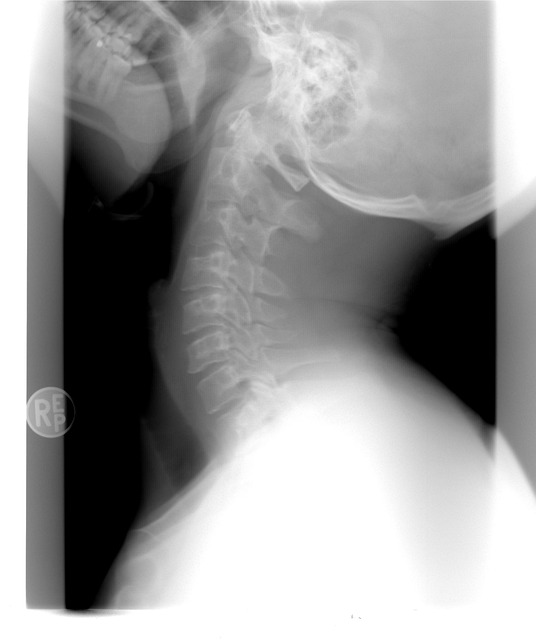

노화에 따라 관절 연골이 닳고 뼈끼리 마찰되면서 염증과 통증이 생긴다. 특히 무릎, 고관절, 손가락 등 사용이 많은 부위에서 흔하다.

- 관절이 움직일 때마다 소리(크레피투스)가 나고 아프면 연골 마모 가능성 있음